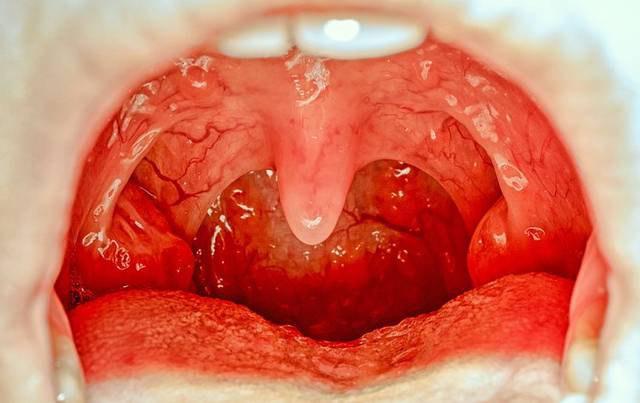

口咽部检查:咽部充血,双侧扁桃体红肿,化脓性扁桃体炎的扁桃体表面可能有脓点,并可连接成片如伪膜状。下颌下淋巴结常肿痛。

口咽部检查:咽部慢性充血,扁桃体大小不定,但是可以看见疤痕和凹凸不平,可能有粘连。患儿常有下颌下淋巴结肿大。